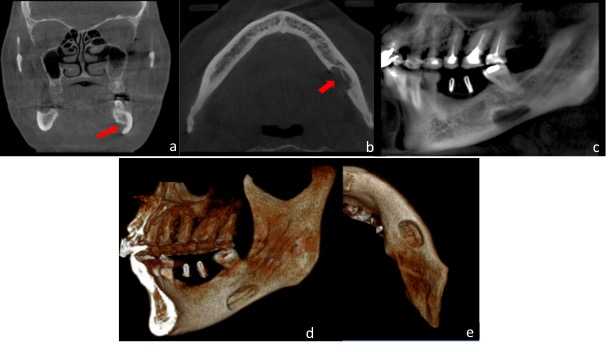

Paciente de sexo femenino, 60 años de edad, asintomática, referida al Centro Imagenológico para el estudio por imágenes previo a la colocación de implantes. A la evaluación en la radiografía panorámica (Figura 1) se evidenció la presencia de una imagen radiolúcida localizada en la zona antegonial del lado derecho, por debajo del canal mandibular, de límites definidos y bordes corticalizados. Al estudio mediante TCHC, se observó en los cortes axial y coronal, una concavidad bien delimitada, dependiente de la tabla ósea lingual que condicionaba el adelgazamiento de la cortical vestibular (Figura 2a- b). En el corte sagital (Figura 2c) y reconstrucciones 3D (Figura 2d) se evidenció la imagen hipodensa bien delimitada en la región antegonial, cursando con adelgazamiento de la basal mandibular, sin afectar la trayectoria del canal mandibular. La imagen muestra signos tomográficos compatibles con COS Tipo II.

Figura 2 FIGURA 2. Reconstrucciones multiplanares de Tomografía Computarizada de Haz cónico donde se observa en a, b y c, vistas axial, coronal y sagital respectivamente, imagen hipodnesa, ubicada por debajo del canal mandibular (flechas rojas). La cavidad es dependiente de la tabla ósea lingual y condiciona adelgazamiento de la tabla ósea vestibular. En las reconstrucciones volumétricas en d. Vista infero-superior, e. Vista Lateral y f. Vista lateral oblicua, se identifica el adelgazamiento de basal mandibular (Flechas rojas).